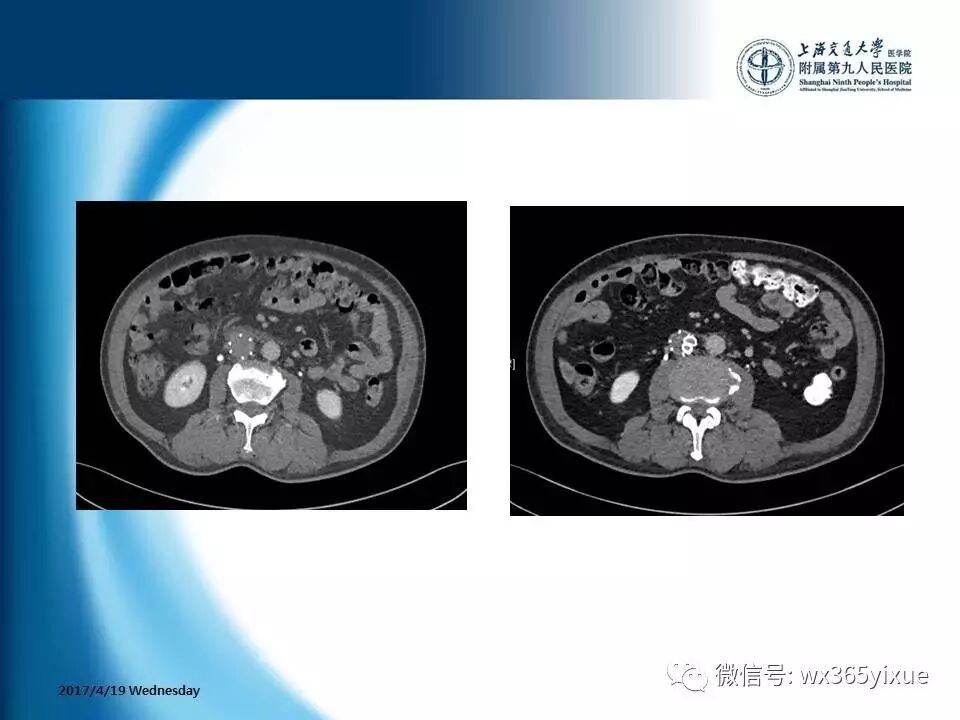

【热点课件】陆信武:滤器相关下腔静脉血栓成的腔内治疗

上海交通大学医学院附属第九人民医院